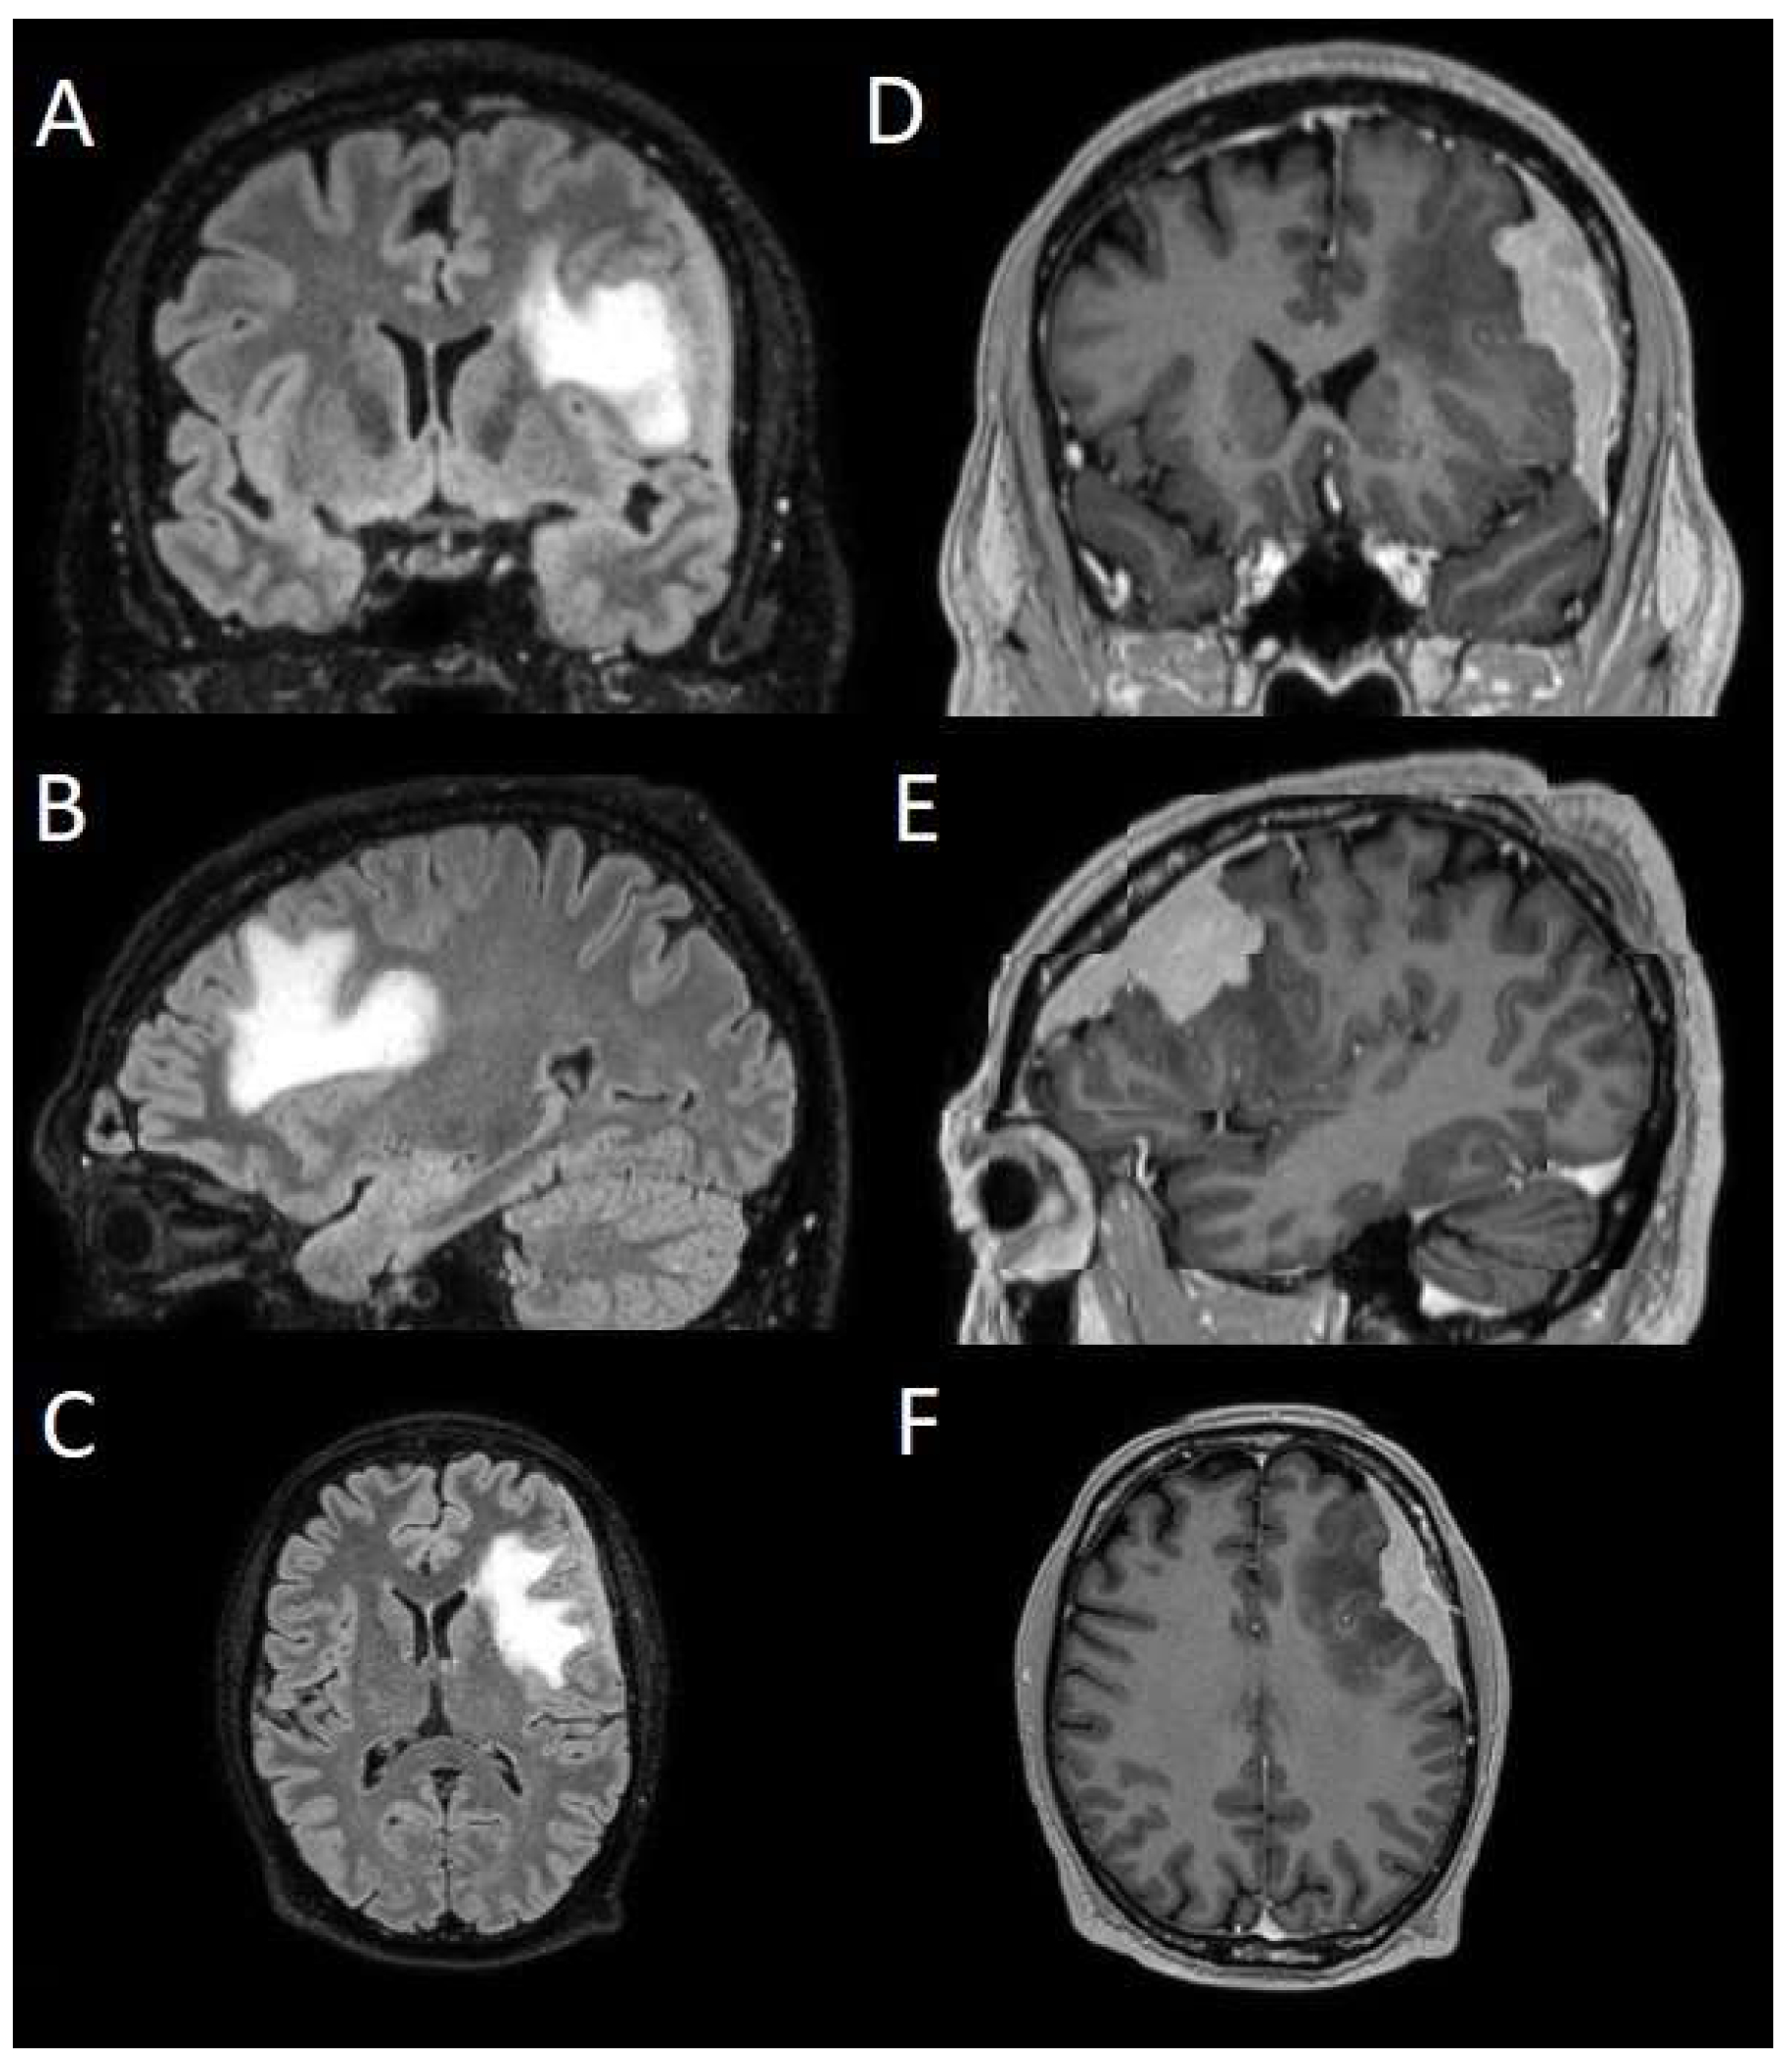

The patients underwent magnetic resonance imaging (MRI) at our center using a 1.5T or 3T Tesla MRI machine (Ingenia 3T, Philips Medical Systems, Best, The Netherlands) with the standard oncological protocol [14]. Specifically for analysis, the sequences collected were T1-weighted with contrast enhancement to estimate tumor volume and conformation and FLAIR (fluid-attenuated inversion recovery) to quantify PE (Figure 1). We manage the preoperative imaging in a DICOM (digital imaging and communications in medicine) format. The images from the T1-weighted sequences with contrast enhancement and FLAIR sequences in the DICOM format were processed through the Slicer website [15]. Tumor and PE segmentation was performed using a voxel-based analysis that integrated automated and manual methods (Figure 2).

The process begins with an automatic thresholding technique to identify initial regions of interest based on intensity values (Figure 2A,E). This is followed by manual refinement to enhance accuracy and delineate precise boundaries (Figure 2B,C,F,G). The final segmentation provides volumetric measurements for both the tumor and the PE, aiding in quantitative analysis (Figure 3). The included patients’ pre- and post-treatment clinical data were retrospectively extracted from our center’s computerized database. Collected data included demographic information, preoperative clinical details (presence or absence of epilepsy, onset symptoms, ASM therapy and number of ASMs taken, and radiological characteristics of the meningioma), and postoperative data (Engel class [16], persistence or discontinuation of ASMs, ASM discontinuation timing, and possible postoperative functional deficits). A single examiner conducted data collection to minimize subjective variability in assessments. Surgical procedures were performed using a transcranial approach under general anesthesia. We excluded cases of surgical resection performed via an endoscopic endonasal approach. Cases of postoperative death (within one year after surgery) were excluded. The extent of resection (EOR) was determined based on the postoperative MRI (usually one month after surgery) and classified according to the Simpson grading system [17]. This study included cases of complete macroscopic meningioma resection (Simpson I, II, and III). Cases with residual tumor persistence or recurrence after surgery (Simpson IV and V) were excluded (Figure 4).

Figure 5. Segmentation process for PE > 1 cm3. (A,E) Automatic thresholding technique to identify initial regions of interest based on intensity values, respectively, for the PE and the meningioma. (B,F) Partially automatic erase of redundant signal with “erase outside” tool. (C) Precisely definition of boundaries of edema through manual erasure, cutting all around the redundant signal inside the tumor. (G) Manual erasing boundaries for tumor volume. (D,H) Final segmented volumes. PE: peritumoral edema.